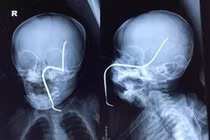

Tại BV, sau khi thăm khám, chụp X-quang, các bác sĩ xác định bệnh nhân bị khuyết sọ vùng đỉnh phải và chỉ định phẫu thuật. Tuy nhiên, do tình trạng trạng của bệnh nhân chưa ổn định nên ca phẫu thuật chưa thực hiện được. Hiện tại, bệnh nhân tiếp tục được chăm sóc, điều trị tại BV.